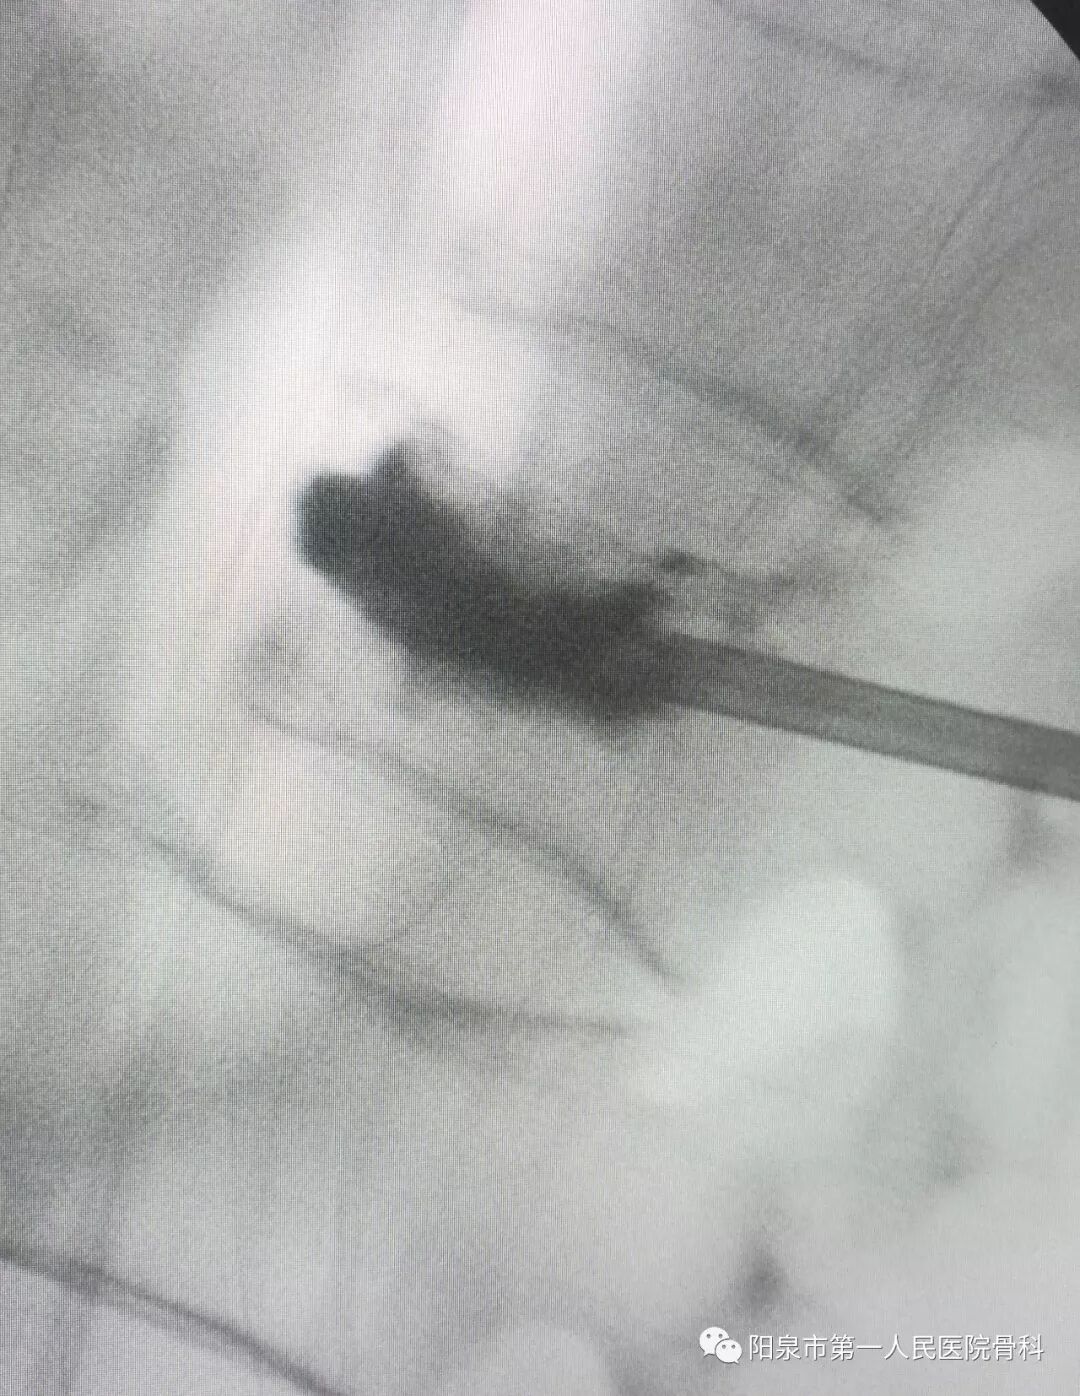

后凸成形术时的球囊撑起显影图像